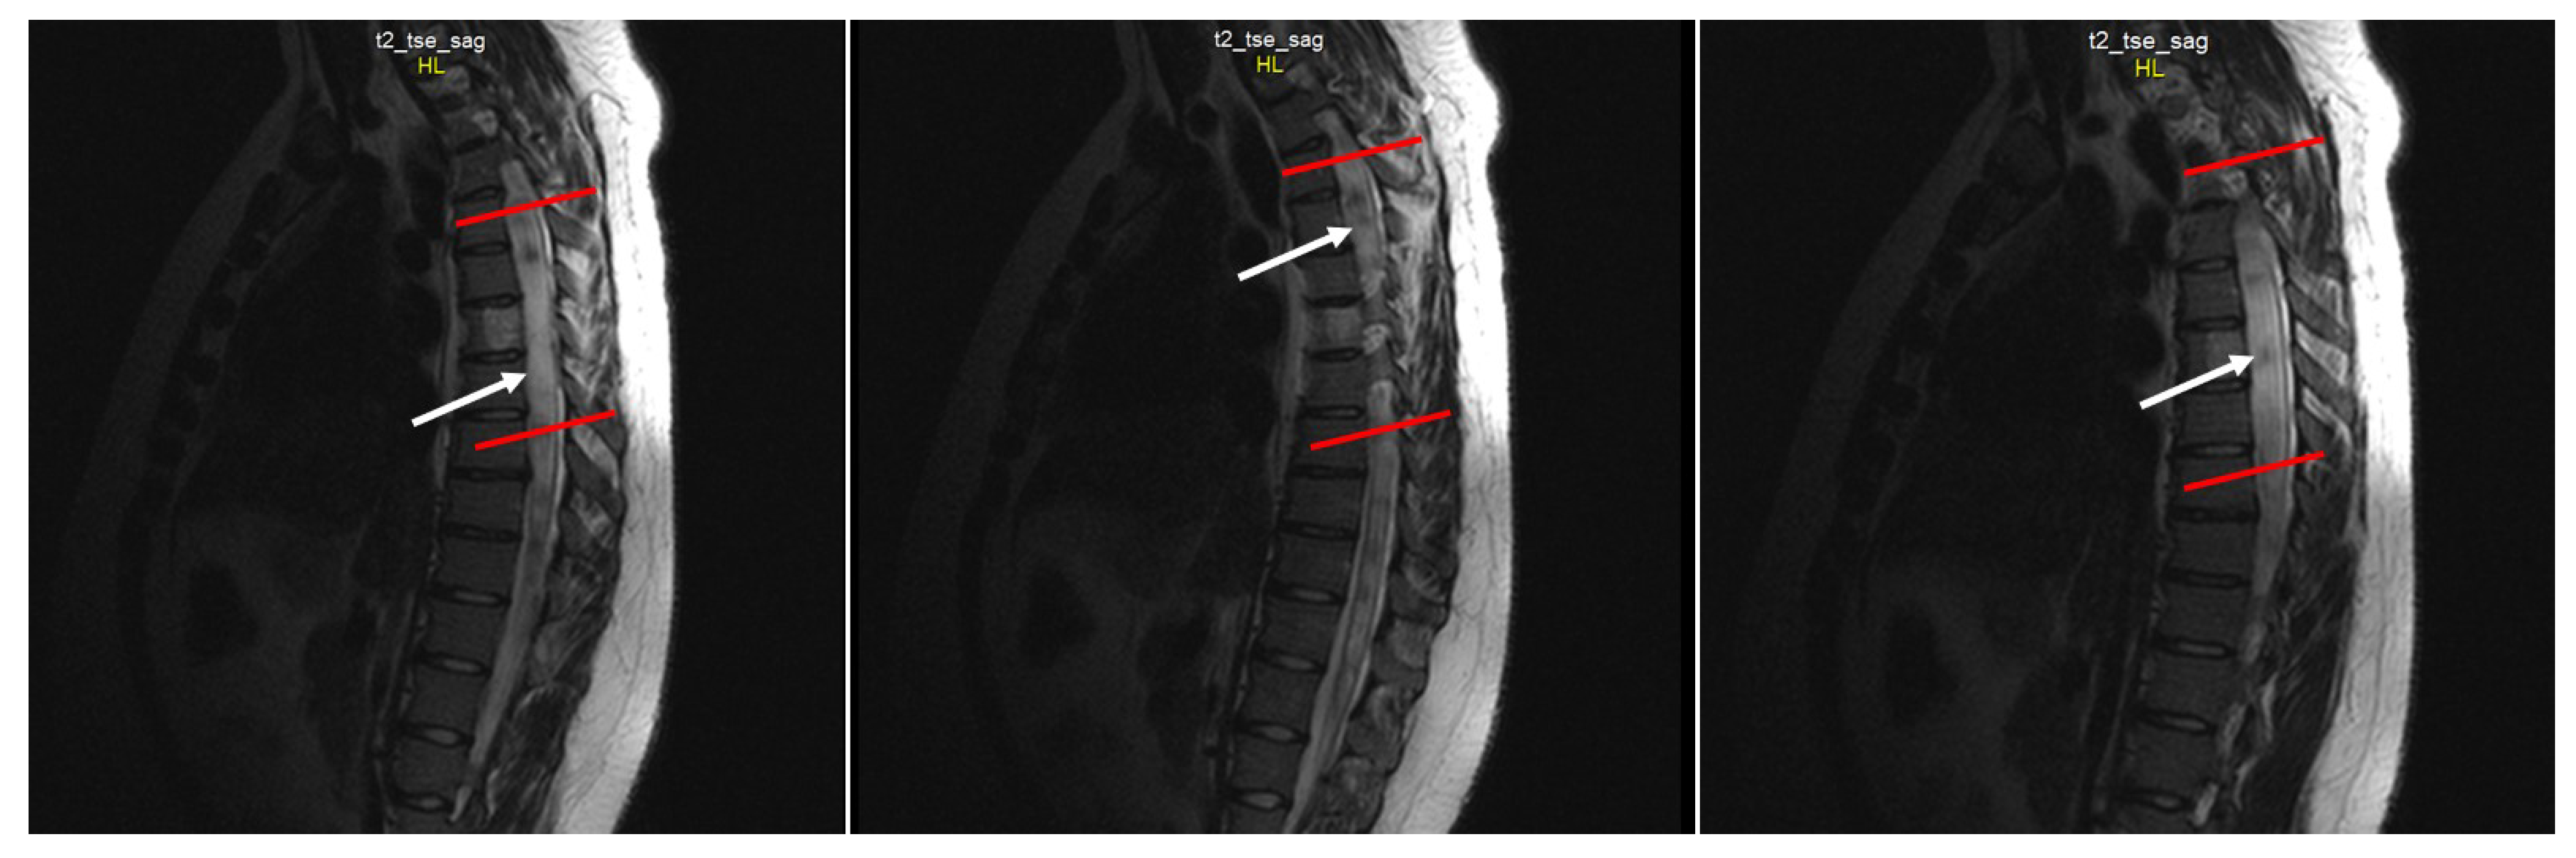

2.4. Neuroimaging